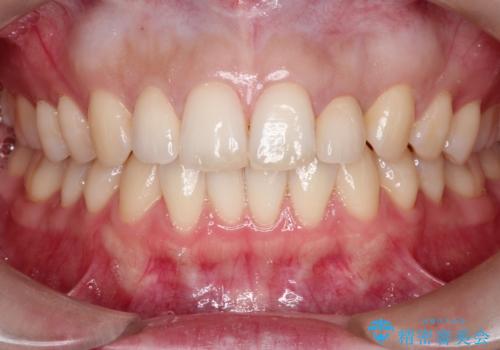

【矮小歯】オールセラミッククラウン

- 側切歯が小さいことを主訴に来院されました。

いくつかの治療の選択肢を説明し、オールセラミッククラウンで治療することとなりました。

長期的に安定した治療を求める場合はオールセラミッククラウンによる治療を提案します。